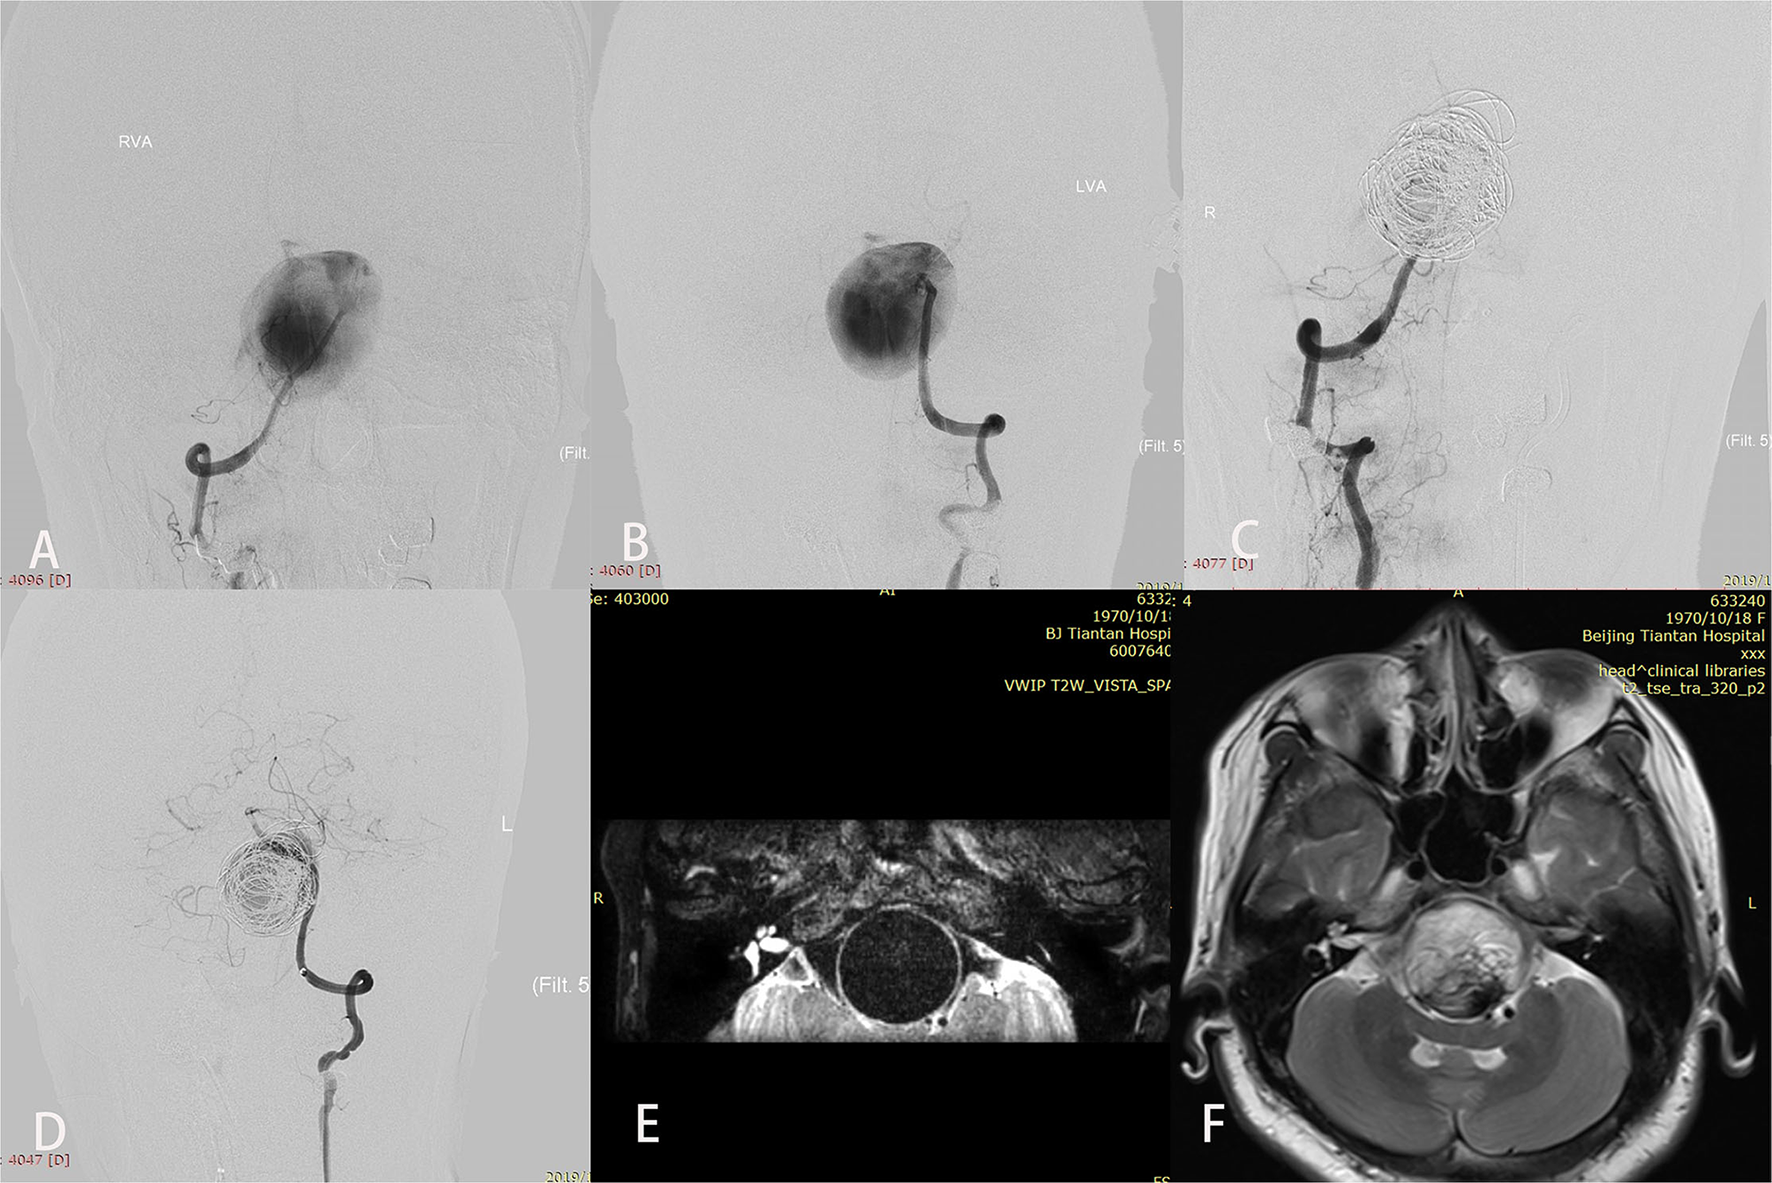

Three patients with giant aneurysms experienced worsened mass effect after treatment; all presented with initial symptoms of brainstem compression. Cases 5 and 19 experienced abducens nerve palsy after the procedure; however, MRI did not show an infarction. At last follow-up, they had fully recovered. Case 17 developed dyspnea because of aneurysmal brainstem compression after treatment and maintained a tracheotomy until he died of severe pulmonary infection 11 months later (Figure 2).

Figure 2

A patient (case 17) with symptoms of mass effect from a giant vertebrobasilar junction aneurysm underwent placement of a single Pipeline embolization device along with coiling and right vertebral artery sacrifice. After treatment, disturbed consciousness and dyspnea developed. Preoperative anteroposterior views of right (A) and left (B) vertebral angiography showed the aneurysm. (C,D) Angiography immediately after the procedure showed successful sacrifice of the right vertebral artery, excellent reconstruction of the basilar artery, and contrast stasis in the lumen of the aneurysm. (E) T2-weighted imaging before the intervention demonstrated a complete flow void within the aneurysm. (F) T2-weighted imaging after treatment showed aneurysmal enlargement and signal inhomogeneity within the aneurysm consistent with thrombosis.